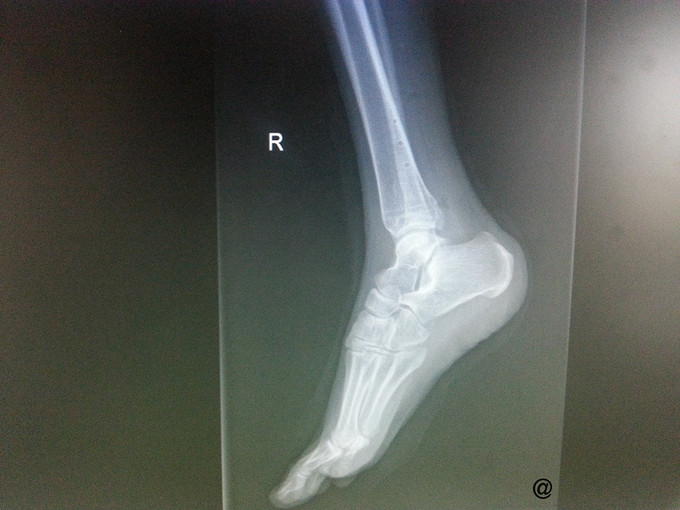

主诉:右三踝骨折ORIF术后一年半,要求取出内固定 病史:患者一年半前因外伤致右三踝骨折,1年前我院行“右三踝骨折ORIF术”。术顺,目前患者术后恢复良好,无切口处疼痛红肿热痛、无畸形愈合,为取出内固定再次入院。

查体:右侧外踝处可见一纵行8cm左右的陈旧性手术疤痕,愈合良好,踝关节无压痛,无肿胀,活动可。四肢肌力、肌张力正常。足趾自主活动良好,末梢血运正常,足背动脉搏动可及,皮肤感觉存在。其他肢体未见明显异常。 辅查:右侧踝关节正侧位片:右侧内外踝骨折内固定术后,内固定器在位,断端对位对线可。

诊断:取除骨折内固定装置(右三踝骨折术后) 处理:右踝关节骨折术后取内固定术

随访:术后2周患者拆线,手术切口愈合好。 讨论:骨折内固定一半选择在1至2年内拆除。请讨论有没有内植物长期不取出有无断裂的风险